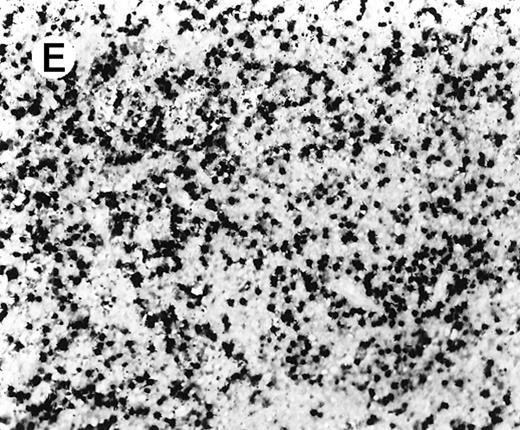

Staining for CD4 and CD8 in spleen from case 2.

(A) The lymphoid infiltrate in the spleen is predominantly CD8+. (B) Staining for CD4 highlights erythrophagocytic histiocytes, whereas the lymphocytes are negative. (C) The small lymphocytes express TIA-1. (D) They are BF1+ and are strongly EBER-1+ (E) (immunoperoxidase stained, hematoxylin counterstained, × 200).

The immunophenotypic features and molecular data are summarized in Table 2. Immunophenotyping was performed on the spleen or liver or both in all cases. The infiltrate in all cases was composed predominantly of CD3+ T cells (Figure3A). CD20 stained attenuated residual B-cell areas in the spleen and only rare scattered B cells were identified within the liver (Figure 3B). Staining for CD4 and CD8 showed that the infiltrate was CD8+ in 2 cases (Figure4A), CD4+ in 2 cases (Figure5A), and in the remaining 2 cases CD4+ and CD8+ cells were noted in approximately equal numbers without clear subset predominance. CD4 highlighted the erythrophagocytic histiocytes (Figure 4B). The lymphocytes in all cases expressed βF1 and TIA-1+ (Figure 4C and D) and were CD56−.

In situ hybridization for EBV using the EBER1 probe showed striking positivity in the majority of the small lymphoid cells in all cases (Figure 4E). Correlation of the EBV positivity with the distribution of CD4/CD8 staining clearly indicated that the EBV-harboring cells were CD8+ in cases 2 and 5 (Figure 4E) and CD4+ in case 4 (Figure 5A-C). In addition, although an admixture of CD4+ and CD8+ cells had been previously noted in case 1, double staining for EBER1 and CD4 confirmed presence of EBV in the CD4+ population, with the CD8+ cells being clearly negative (Figure 6A,B). In the other 2 cases (cases 3 and 6), it was difficult to ascertain whether the CD4+ or CD8+ cells harbored the EBV, and double staining was not contributory.